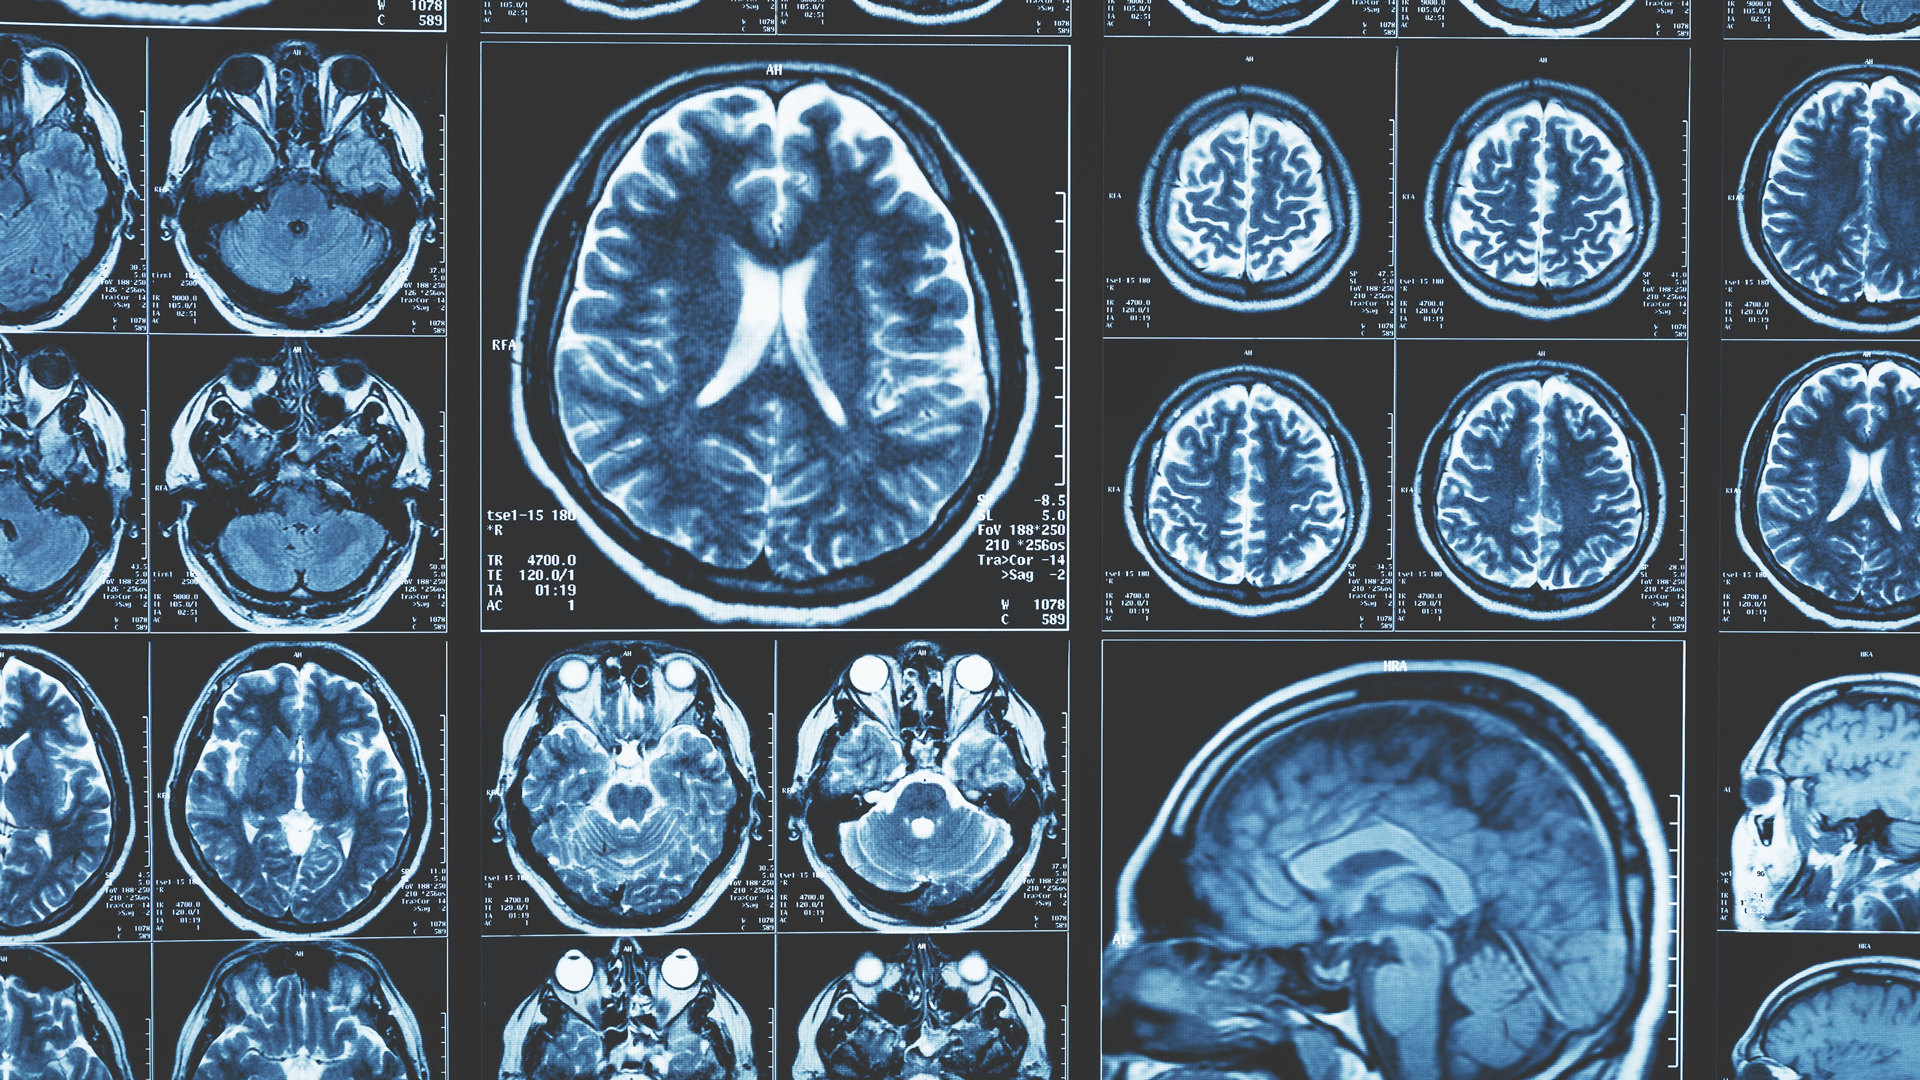

The PMDC Pilot Grants program supports translational research initiatives looking to transform the clinical care of patients with movement disorders. (Photo courtesy of Adobe Stock)